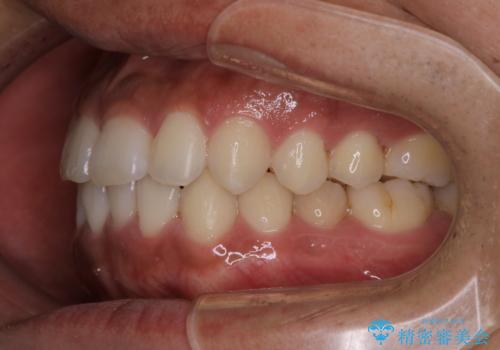

- 上下の前歯のがたつきが気になるとご相談にいらした方です。光加速矯正装置(オルソパルス)を用いて短期間で仕上げることが出来ました。

一般的に噛む力が強い方は矯正治療に時間がかかると言われてます。光加速矯正装置(オルソパルス)を用いることで短期間で仕上げることができました。